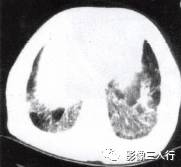

胸部影像常呈肺段或肺叶急性炎性实变。影像实变期表现为密度均匀的致密影,在实变 区中可见空气支气管征。其病理基础是由于广泛的肺泡腔内炎性渗出,肺充气明显减少,使 正常充气的各级支气管与实变的肺泡构成鲜明的对比,形成支气管充气征。见图4至图6。 医学百科网 | YxBaike.Com